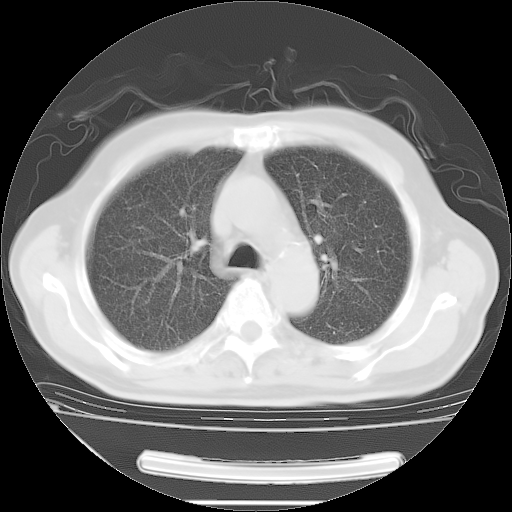

胸腹部CT,诊断意见:左上肺叶钙化灶、左侧胸膜局限性增厚并钙化、胆囊炎。描述部分肺组织呈磨玻璃样改变。